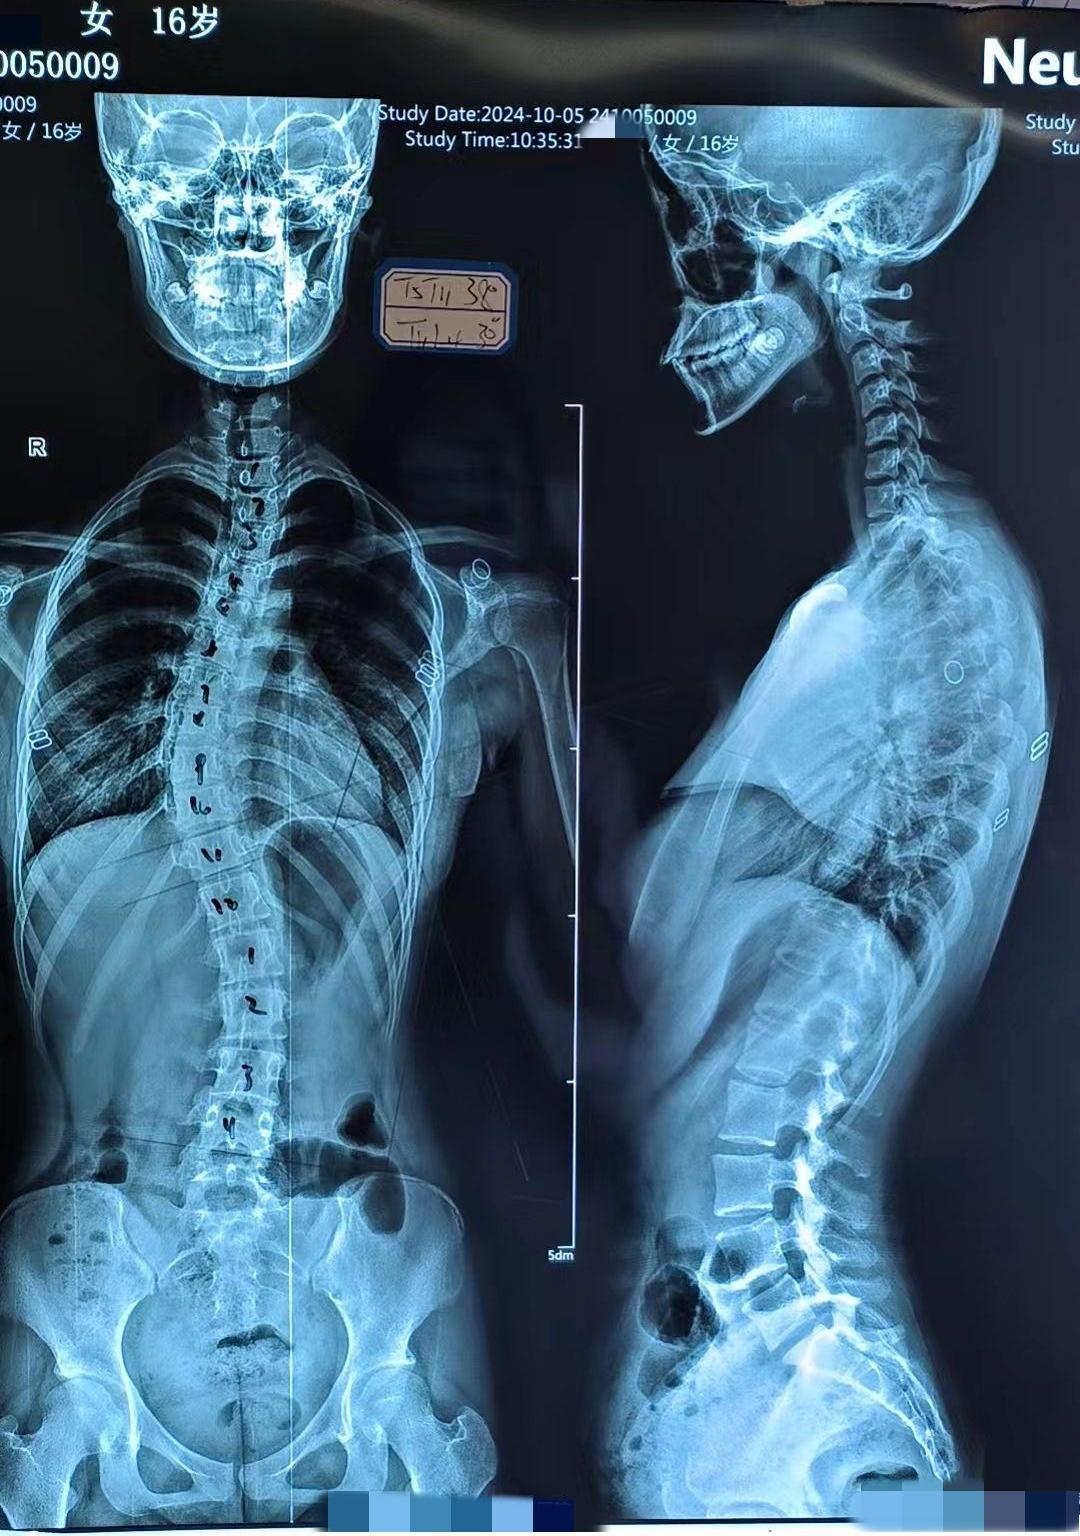

分享一例青少年重度脊柱侧弯案例,患者2年前发现侧弯,当时就有